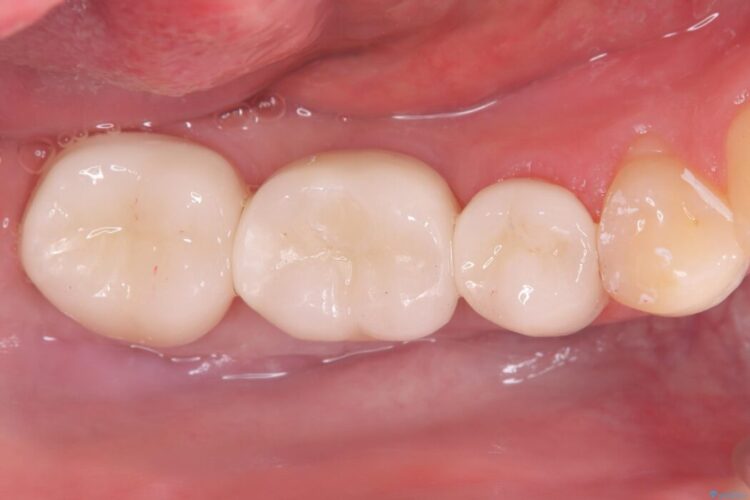

ブリッジを外し、欠損している6番にインプラントを埋入。土台となっていた5番と7番は、セラミッククラウンで修復。

インプラント周囲の歯肉が薄かったため、FGG(遊離歯肉移植術)を行い、長期安定に不可欠な「角化歯肉」を確保しました。